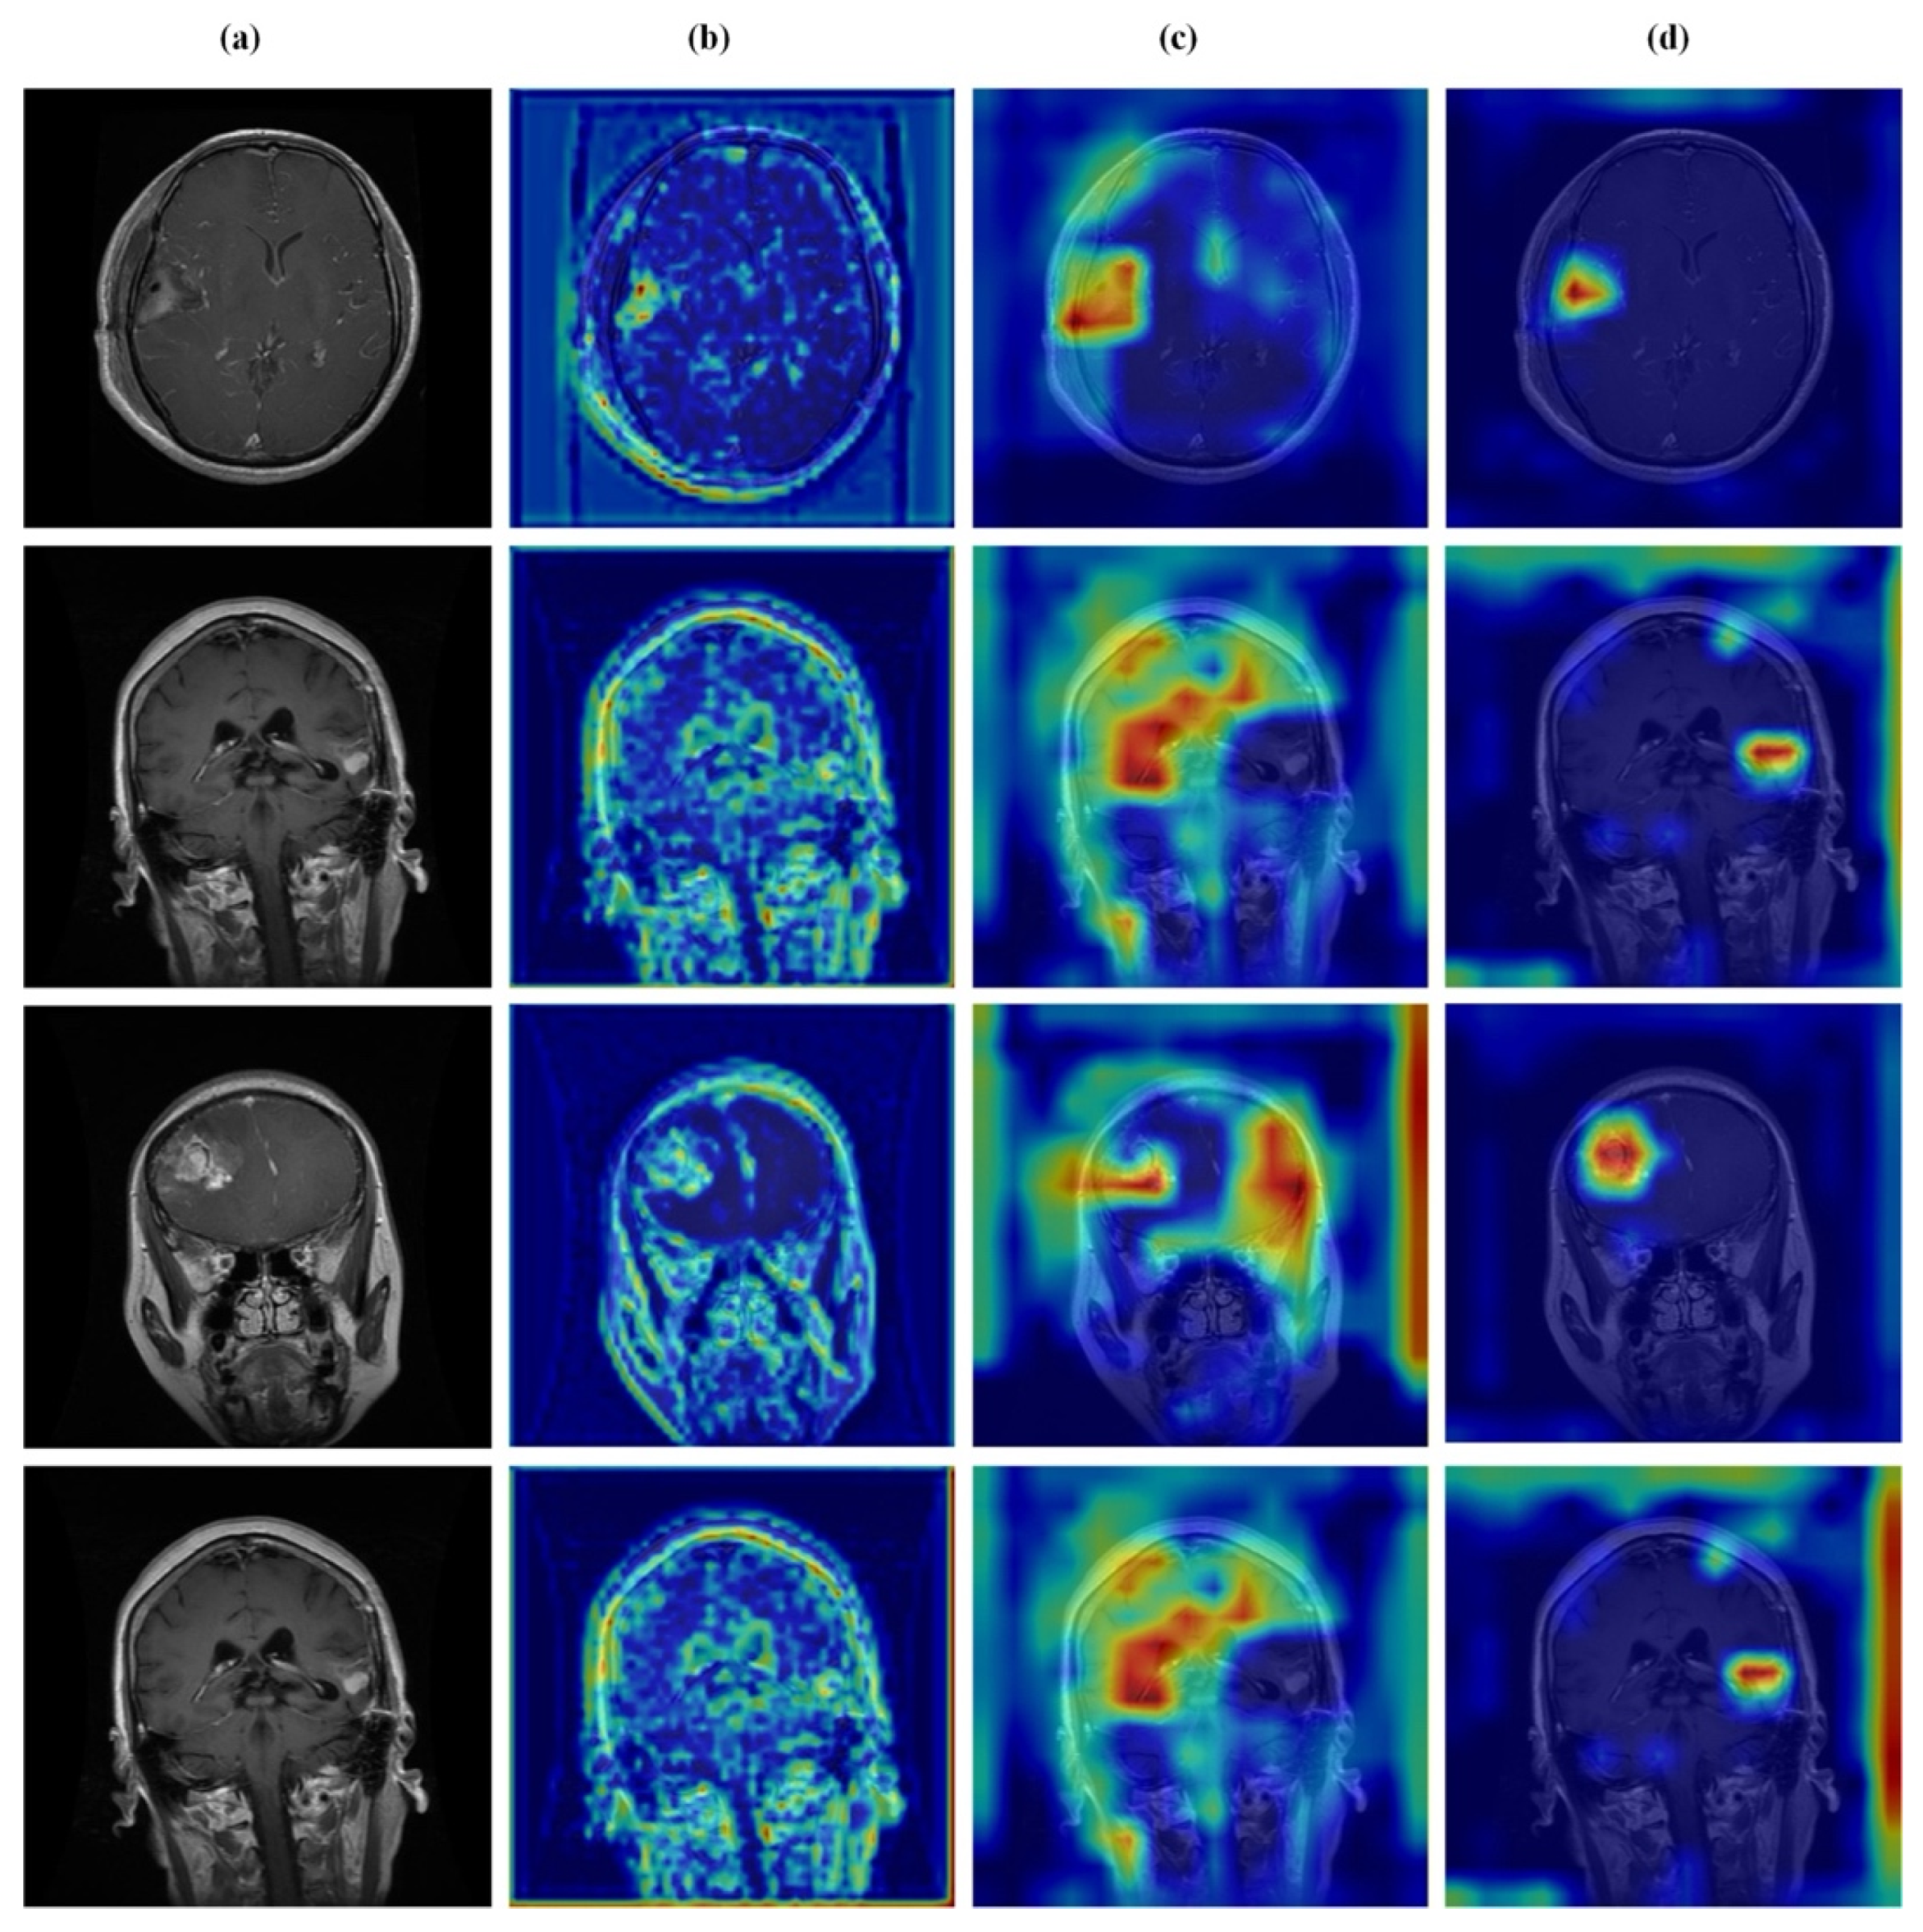

4.7. Feature Learning Analysis

Figure 12, Figure 13, Figure 14 and Figure 15 present Grad-CAM visualizations that trace the hierarchical feature learning of the proposed model across the four classes. Columns are organized as (a) input, (b) high-level features, (c) mid-level features, and (d) low-level features. In (d), the network emphasizes primitive cue edges, intensity transitions, and fine textures capturing sulcal boundaries, skull edges, and generic tissue patterns. Progressing to (c), activations become more structured and context-aware, highlighting coherent anatomical regions and diffuse hyperintense areas that provide spatial context for lesion localization. At (b), class-discriminative focus emerges with responses that contract tumor-centric hotspots for glioma and meningioma and to the sellar region for pituitary cases, while no_tumor images exhibit suppressed high-level responses, reflecting the model’s rejection of false lesion cues. This bottom-to-top progression from generic edges to task-specific evidence explains the model’s improved decision reliability and aligns with the multi-task design that encourages precise, clinically meaningful attention.

Figure 14.

Visual representation of feature activations in meningioma tumor cases. (a) input, (b) low-level features, (c) mid-level features, and (d) high-level features.

Figure 15.

Visual representation of feature activations in pituitary tumor cases. (a) input, (b) low-level features, (c) mid-level features, and (d) high-level features.